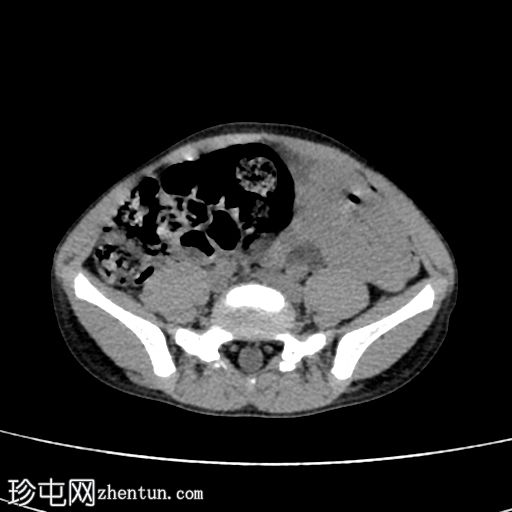

轴位增强CT(门静脉期)

2.jpg

在这张多期增强CT图像中,我们可以观察到肾盏、肾盂以及左侧输尿管全程扩张。

未见感染或其他相关征象。